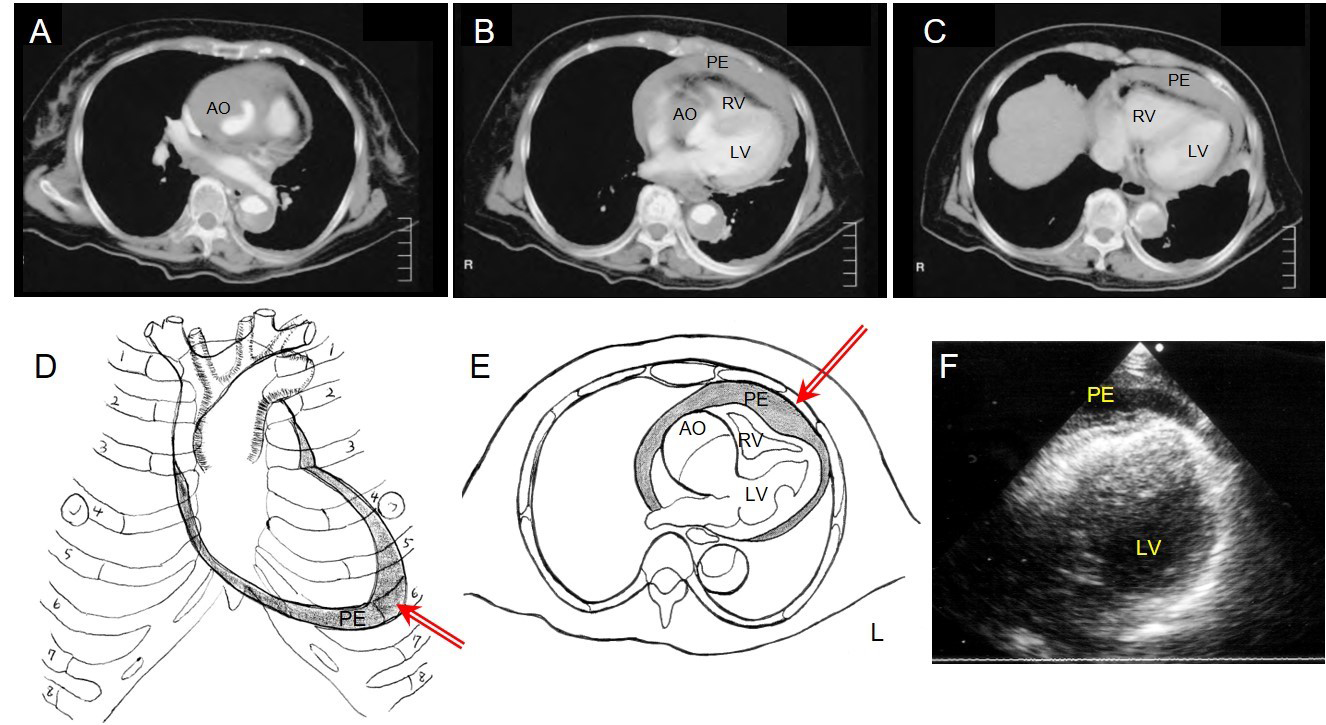

Hayashi et al offered detailed descriptions of their procedure. With the patients in a prone position and under local anaesthesia, an 8 Fr pigtail drainage catheter with multiple side holes was inserted into the pericardial space (PS) under ultrasound guidance [16]. In acute cardiac tamponade caused by AADA, additional pericardial effusion (PE) accumulated around the apex of the heart rather than just above the diaphragm (Figure 1D). Usually, PE was thickest just beneath the skin of the 4th or 5th intercostal space and on or just inside the left mid-clavicular line. Before CPD, the thickest point was marked up on the skin using echocardiography (Figure 1F). As described in Figure 1, puncture was performed from the marked-up point at a 90° angle to the skin, with the needle carefully advanced vertically to the PS. Within 3.0 cm from the skin, the point of the needle was able to penetrate the PS. To avoid complications such as laceration of the coronary artery, vein, or myocardium, the PE needs to be greater than 10 mm in thickness, and the needle should be inserted meticulously. If the needle is advanced laterally, it could cause injury to the lung and pneumothorax. This procedure took 5.3±1.8 minutes. Aspiration of the PE started after the catheter had been placed into the PS. At the beginning, 5 ml to 10 ml of haemopericardium was aspirated and changes in blood pressure were closely observed to prevent excessive elevation of blood pressure. The drainage volume was controlled through intermittent aspiration, using a 10 ml syringe and 5 to 10 ml of aspiration each time, to maintain systolic blood pressure at around 80 to 90 mmHg. After CPD was performed and circulation was restored, the patients were transferred to the operating room to undergo immediate aortic repair. The time interval between CPD and surgery was 58.2±25.0 minutes [16].

Figure 1. Controlled pericardial drainage for critical cardiac tamponade with acute type A aortic dissection.

A), B) & C) Thoracic computed tomography of patient 1 demonstrates AADA with massive pericardial effusion with compression of the right ventricle.

D) Schematic illustration demonstrates accumulation of the pericardial effusion of AADA in a prone position, and the red arrow shows the point and direction of the CPD.

E) Schema demonstrates AADA with massive pericardial effusion and the red arrow shows the angle of the puncture is 90° to the skin.

F) Ultrasound findings from the 5th costal space show pericardial effusion just beneath the skin.

PE: pericardial effusion; AO: aorta; LV: left ventricle; RV: right ventricle